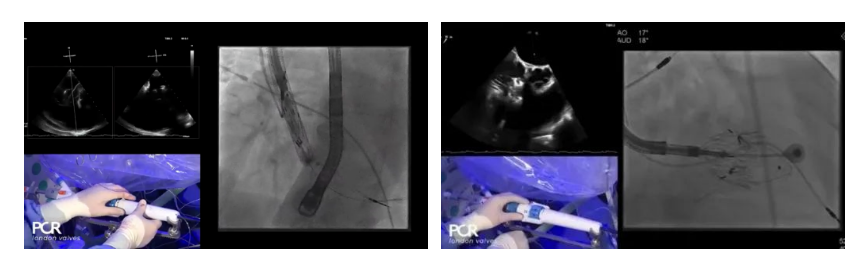

在Thomas Modine教授的線上指導(dǎo)下,德國Mainz中心Ralph Stephan von Bardeleben教授完成了LuX-Valve Plus經(jīng)血管三尖瓣置換系統(tǒng)在其所在中心的首例植入,術(shù)后Stephan教授高度贊揚LuX-Valve Plus人工三尖瓣瓣膜“植入過程高度可控,安全有效”。接受治療的是一例82歲的高齡男性患者,術(shù)前NYHAⅢ級,因復(fù)發(fā)心衰入院,有逾5年的慢性房顫病史。這例患者因特殊的解剖結(jié)構(gòu)以及較大的三尖瓣瓣環(huán),有起搏器植入史,被所有其他經(jīng)導(dǎo)管三尖瓣修復(fù)或置換器械的臨床排除在外,因此等了一年半才等到此次LuX-Valve Plus的手術(shù)機會,實屬不易。

手術(shù)在全麻狀態(tài)下開展,采用經(jīng)右側(cè)頸靜脈入路的方式將輸送器送入患者心臟內(nèi),在TEE及DSA引導(dǎo)下調(diào)整輸送器頭端角度,使得輸送器與三尖瓣瓣環(huán)平面垂直。在輸送器進入右心室后釋放室間隔錨定裝置,而后釋放瓣葉夾持件(2個耳片結(jié)構(gòu))成垂直狀態(tài)。在TEE及DSA確定夾持件固定至三尖瓣葉根部且位于右室側(cè)后釋放人工瓣心房側(cè)盤片。隨后調(diào)整瓣膜同軸性以及室間隔錨定件位置(貼合室間隔),前推藏針管并固定,進而釋放室間隔錨定裝置,并再次確認(rèn)瓣膜位置、穩(wěn)定性及同軸性,合攏輸送鞘后撤出輸送器,完成LuX-Valve Plus人工三尖瓣瓣膜的植入。